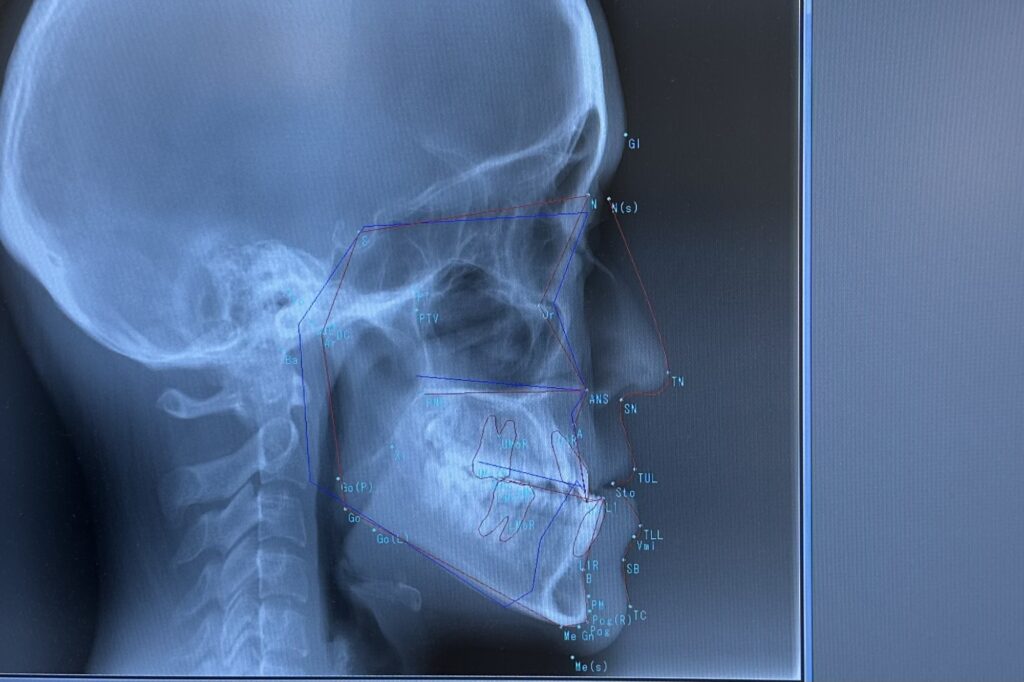

手術が必要かどうかは、見た目だけで判断することはできません。

レントゲンや口腔内の検査を行い、噛み合わせのズレが「歯によるものか」「顎の骨によるものか」を詳しく確認します。その結果をもとに、矯正治療のみで対応できるのか、外科的な治療を併用したほうがよいのかを判断します。

まずはご自身の噛み合わせがどのタイプなのかを知ることが、治療の第一歩になります。